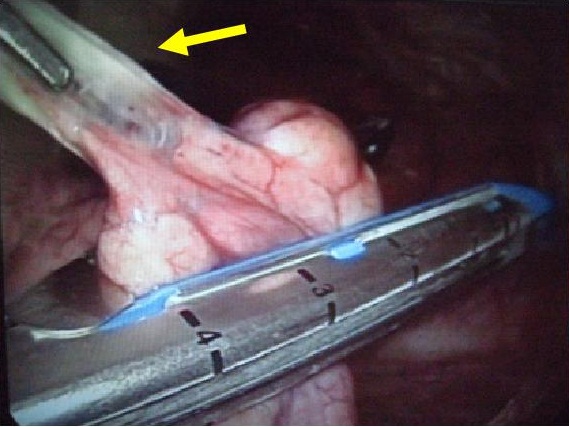

自然気胸の術中所見

術中写真自動縫合器による肺嚢胞(ブラ)切除(肺部分切除)

自動縫合器による肺切除

肺切除後の状態